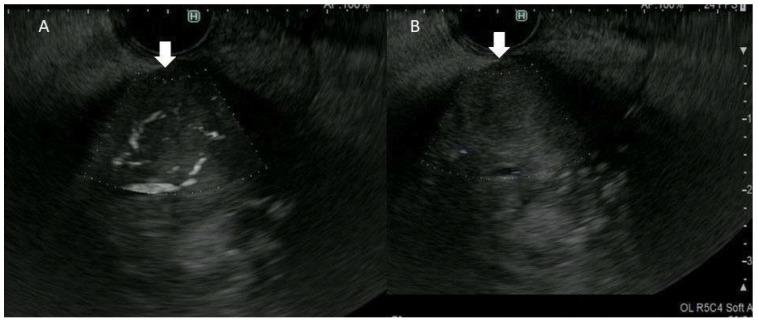

Detective flow imaging endoscopic ultrasonography (DFI-EUS) is an innovative imaging modality that was developed to detect fine vessels and low-velocity blood flow without contrast agents. We evaluate its utility for the differential diagnosis of gallbladder lesions and intraductal papillary mucinous neoplasms (IPMNs). We enrolled patients who underwent DFI-EUS, e-FLOW EUS, and contrast-enhanced EUS for gallbladder lesions or IPMNs. The detection of vessels using DFI-EUS and e-FLOW EUS was compared with that via contrast-enhanced EUS and pathological findings. The vessel pattern was also categorized as regular or irregular. Of the 33 lesions included, there were final diagnoses of 13 IPMNs and 20 gallbladder lesions. DFI-EUS was significantly superior to e-FLOW EUS for discriminating between mural nodules and mucous clots and between solid gallbladder lesions and sludge using the presence or absence of vessel detection in lesions ( = 0.005). An irregular vessel pattern with DFI-EUS was a significant predictor of malignant gallbladder lesions ( = 0.002). DFI-EUS is more sensitive than e-FLOW-EUS for vessel detection and the differential diagnosis of gallbladder lesions and IPMNs. Vessel evaluation using DFI-EUS may be a useful and simple method for differentiating between mural nodules and mucous clots in IPMN, between solid gallbladder lesions and sludge, and between malignant and benign gallbladder lesions.

侦探流成像内镜超声检查(DFI-EUS)是一种创新的成像方式,其开发目的是在不使用造影剂的情况下检测细小血管和低速血流。我们评估其在胆囊病变和导管内乳头状黏液性肿瘤(IPMN)鉴别诊断中的效用。我们纳入了接受DFI-EUS、e-FLOW EUS和对比增强EUS检查的胆囊病变或IPMN患者。将DFI-EUS和e-FLOW EUS检测血管的情况与对比增强EUS及病理结果进行比较。血管形态也分为规则或不规则。在纳入的33个病变中,最终诊断为13个IPMN和20个胆囊病变。在通过病变中血管检测的有无来鉴别壁结节与黏液凝块以及实性胆囊病变与胆泥方面,DFI-EUS显著优于e-FLOW EUS(P = 0.005)。DFI-EUS显示的不规则血管形态是恶性胆囊病变的显著预测指标(P = 0.002)。DFI-EUS在血管检测以及胆囊病变和IPMN的鉴别诊断方面比e-FLOW-EUS更敏感。使用DFI-EUS进行血管评估可能是一种有用且简单的方法,可用于鉴别IPMN中的壁结节与黏液凝块、实性胆囊病变与胆泥以及恶性与良性胆囊病变。